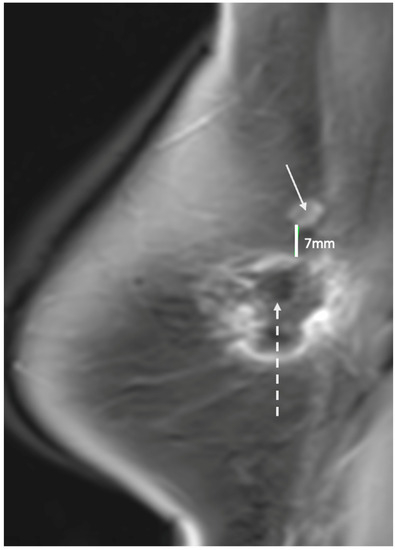

Ultrasound of the breast. Office-based cryoablation is optimized for treatment of ultrasound-visible breast cancers. Consequently, breast ultrasound should be performed of all suspicious imaging abnormalities to assess eligibility for ultrasound-guided cryoablation. Ultrasound permits assessment of the cancer’s proximity to the overlying skin and underlying chest wall and also enables detection of changes in adjacent tissue architecture (e.g., edema, tissue distortion, extension of tumor into adjacent ducts) and could indicate the presence of more extensive disease that would need to be incorporated into the treatment plan (Figure 2). Proximity (<5 mm) of a cancer to the skin is generally regarded as a contraindication to cryoablation, but a safe skin distance can sometimes be created using hydrodissection or injection of saline between the tumor and overlying dermis.

Figure 2.

(A) shows dark, dominant, irregular mass encircled by hash marks with intraductal tumor extensions (dark bands bracketed by paired arrows) extending from left and right sides of dominant mass. (B) shows dark, irregular dominant mass (arrow) surrounded by peri-tumoral edema outlined by hash marks.